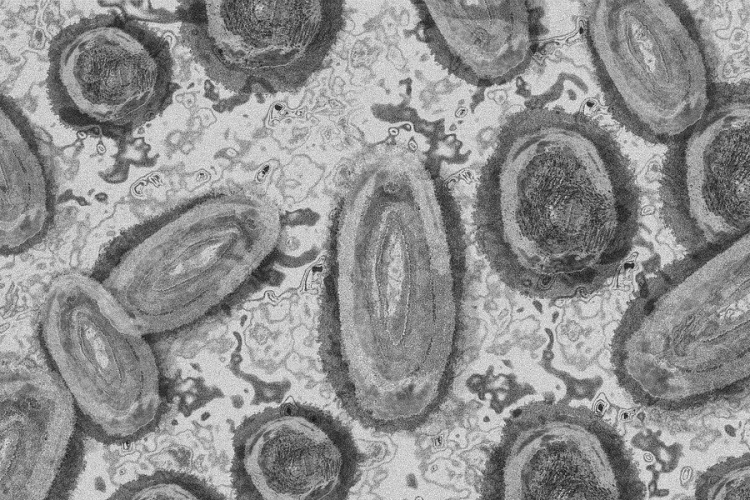

Tovább nőtt a majomhimlő-fertőzöttek száma Magyarországon

Újabb két embernél igazolt majomhimlő-fertőzést a Nemzeti Népegészségügyi Központ (NNK) a 33. héten - augusztus 15-től 21-ig -, ezzel 64-re nőtt a magyarországi esetek száma.